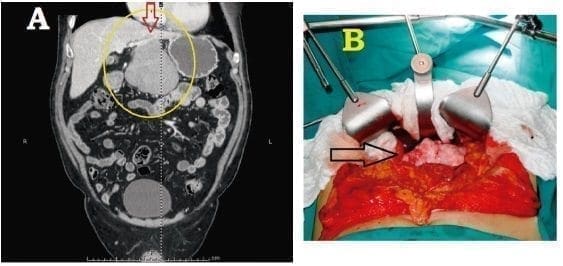

La resección quirúrgica es la única opción terapéutica disponible en el tumor fibroso solitario del hígado, por lo cual, fue el tratamiento utilizado en todos los casos reportados; no obstante, no está exenta de graves complicaciones 35. Se ha descrito una gran variedad de procedimientos quirúrgicos para la remoción del tumor fibroso solitario del hígado; en todos los casos se debe lograr una resección R0, la cual mejora el pronóstico de supervivencia a los cinco años 36. Cuando el tumor comprometa una parte del lóbulo hepático derecho o del izquierdo, la solución ha sido una hepatectomía formal derecha o izquierda, o alguna combinación de segmentectomías, según el grado de compromiso hepático 7, 8,10-20,23-29,35. En un caso, el tumor fibroso solitario del hígado pendía del lóbulo caudado, por lo cual la resección del pedículo tumoral se consideró suficiente (figura 4).

Figura 4. A. Tumor fibroso solitario del hígado que “cuelga” del lóbulo caudado. B. Vista del mismo tumor in situ, antes de la resección quirúrgica.